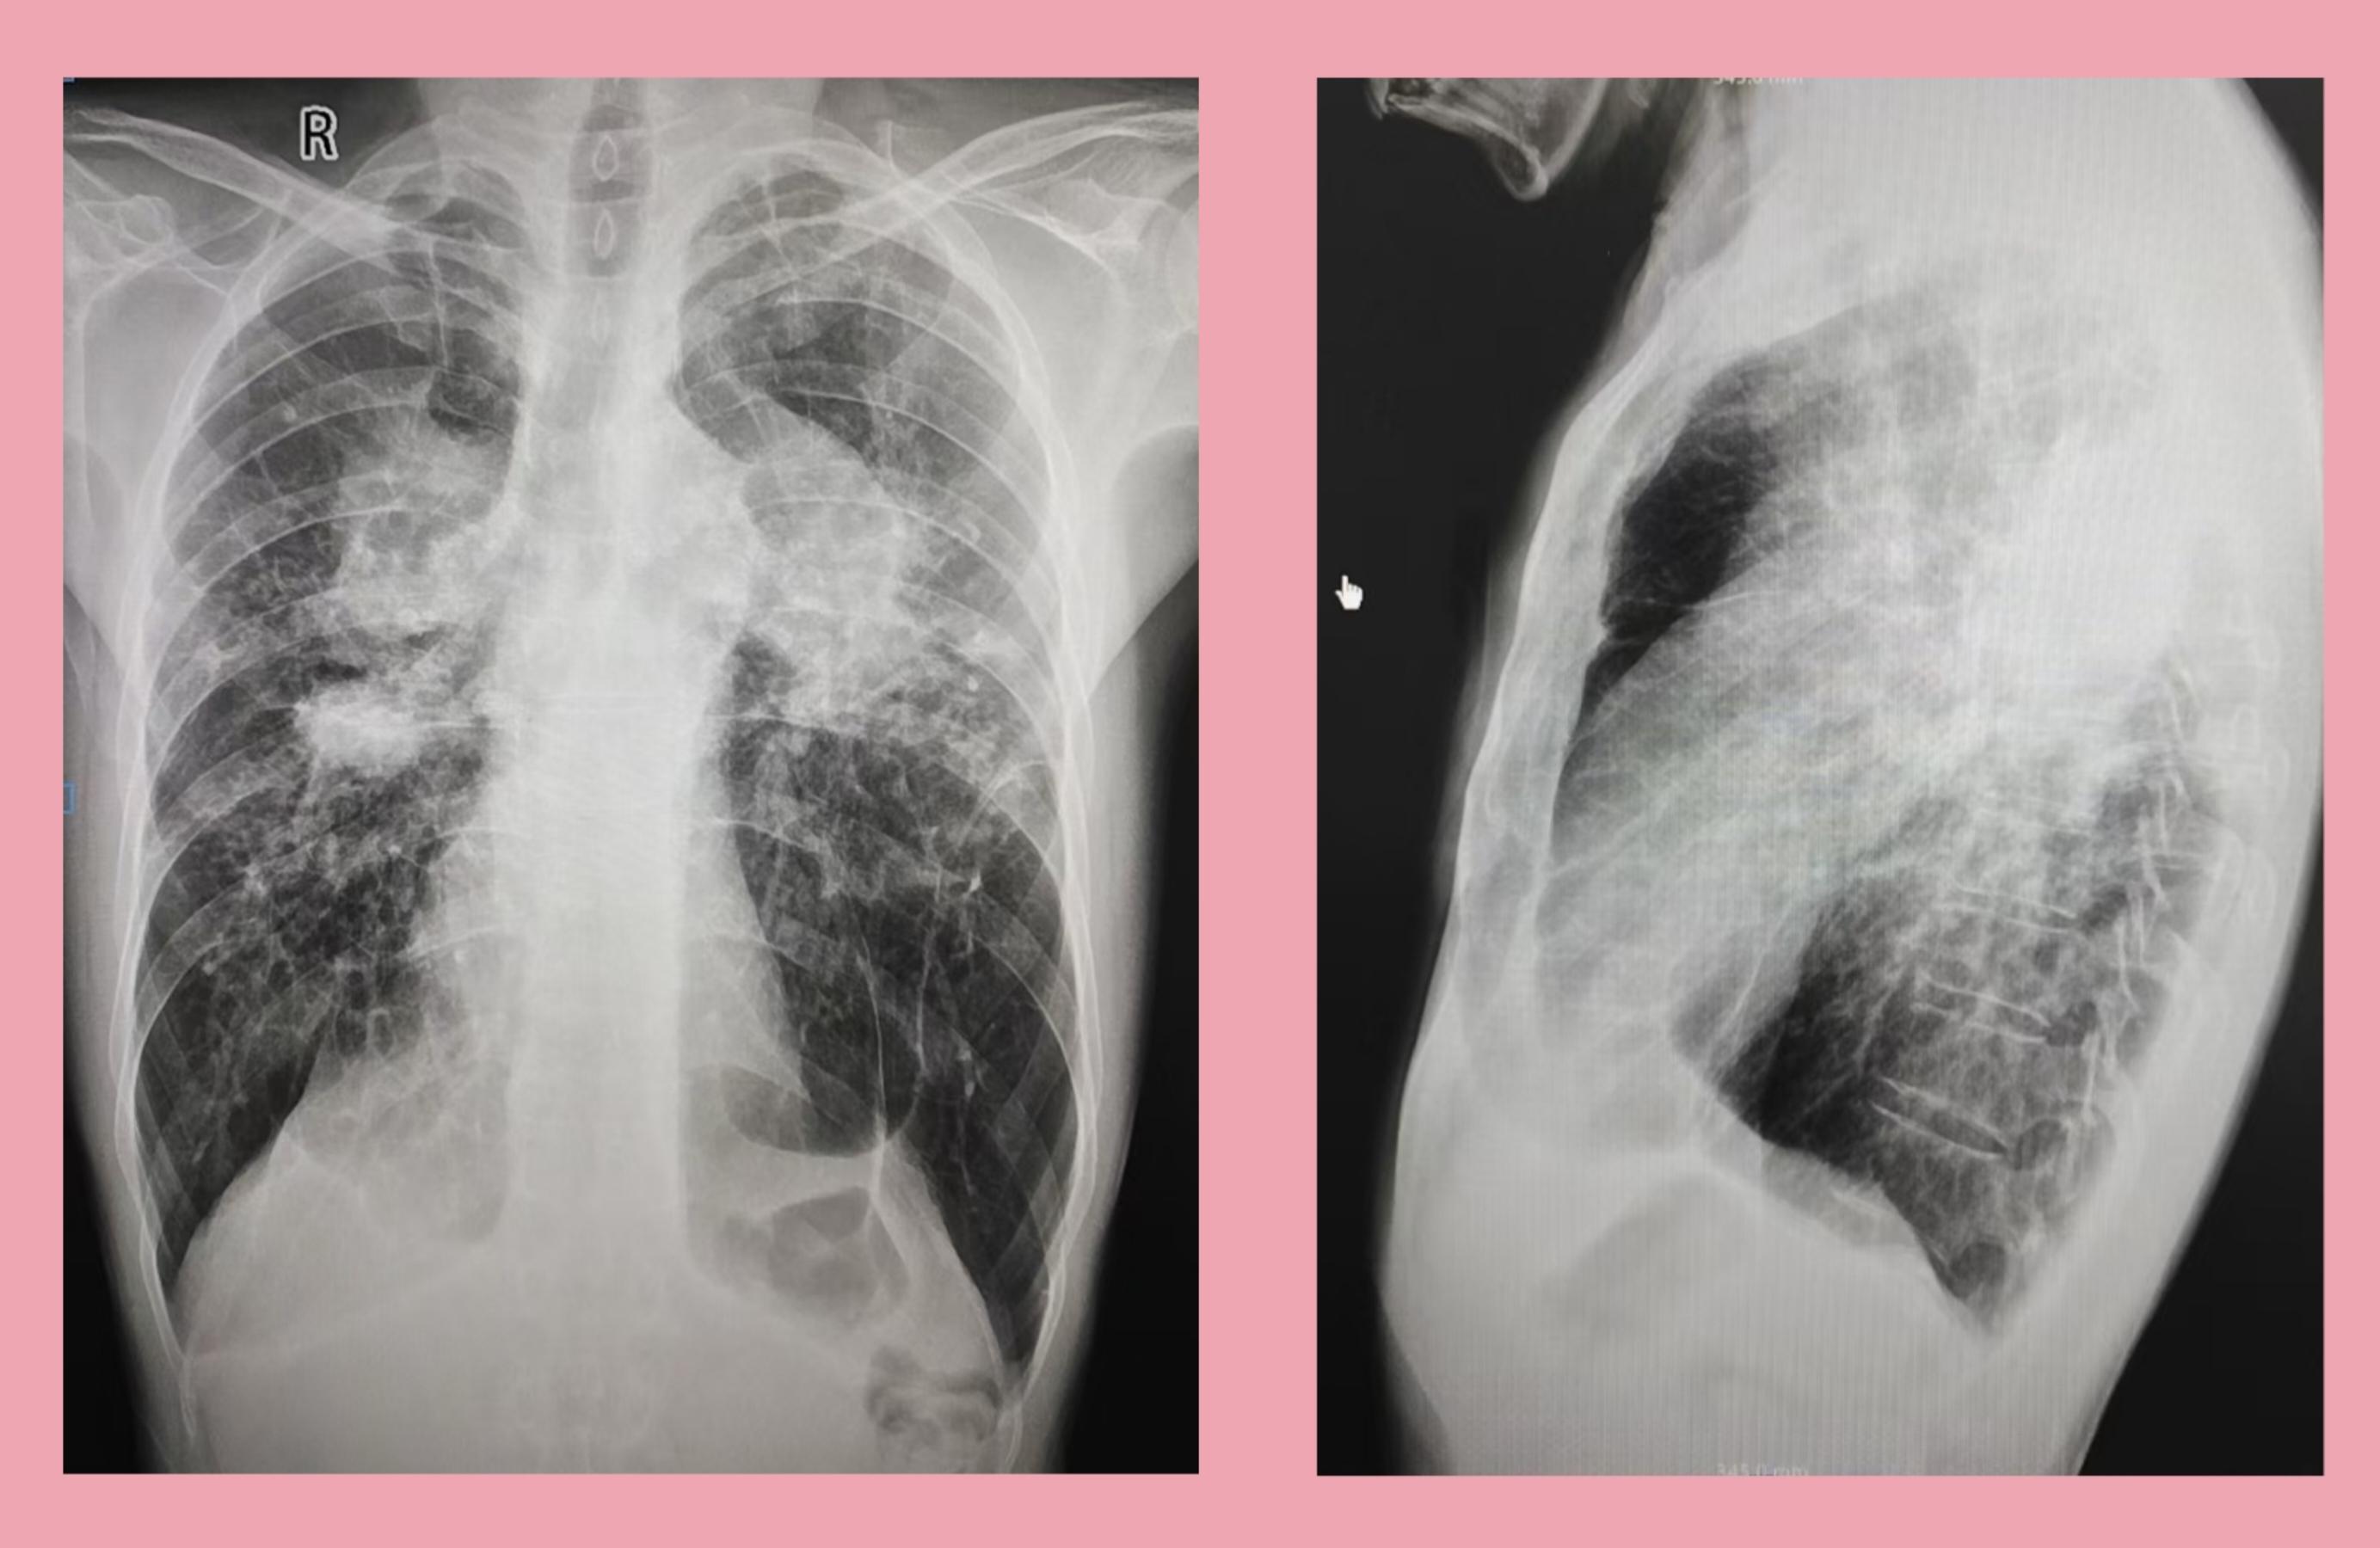

尘矽肺dr,ct影像学表现

胸片病变典型尘肺表现影像描述